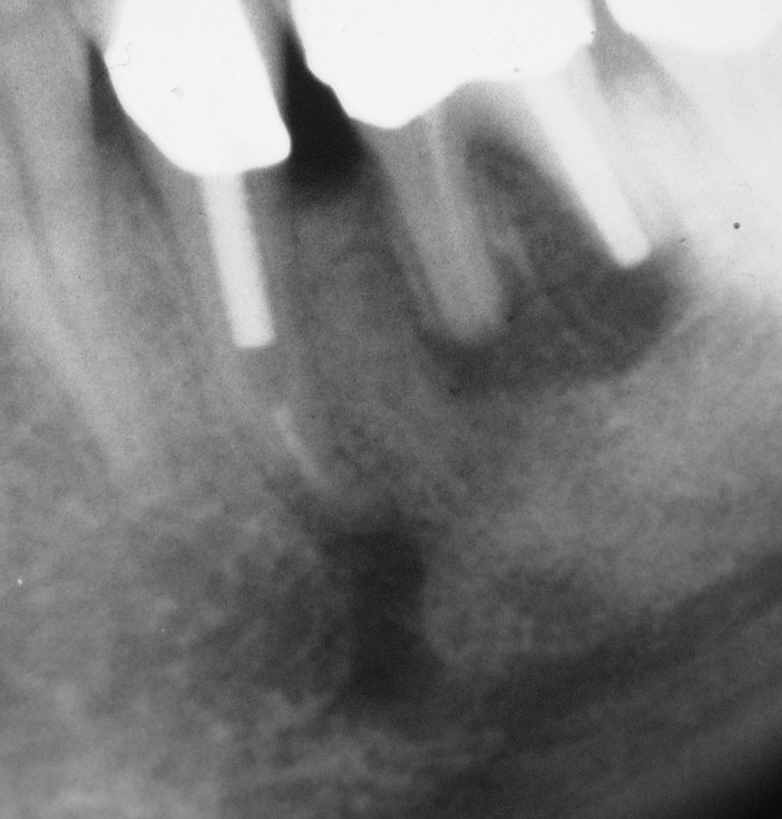

Dezember 1992, unmittelbar vor VitE an 35 und Resektion an 36 (Klick!)

Die untere Bildreihe zeigt eine röntgenologische Verlaufskontrolle nach 10 Jahren. Am 46 ist es gut gegangen, am 36 völlig in die Hose, bei 44 ist es zur Ausbildung eines großen Granuloms gekommen. Besonders interessant ist der 35. Hier hat sich über die Jahre ganz offensichtlich ein klinisch symptomloses Gleichgewicht zwischen Angriff durch belassene Bakterien und Abwehr durch das Immunsystem des relativ jungen Patienten (Mitte 30) entwickelt. Eine Reinfektion im Sinne eines koronalen Lecks ist in diesem Falle aufgrund des Stiftes und der Krone mit der erforderlichen großen Wahrscheinlichkeit auszuschließen.

Was das sofortige Abfüllen in einer Sitzung bei VitE betrifft, so macht dieser Fall deutlich, dass das mit der notwendigen Sicherheit nur  im Falle einer astreinen VitE möglich ist, wie der Erfolg am 46 zeigt. Das Problem ist aber, dass man klinisch in keinem Fall sicher entscheiden kann, ob nicht bereits in Teilbereichen des Hohlraumsystems eine Gangrän (sog. "partielle Gangrän") vorliegt, die für eine vorhersagbare, sichere Ausheilung eine vollständige, sorgfältige Desinfektion mit einem potenten Desinfizienz erfordert. Das Vorliegen einer solchen "Partiellen Gangrän" machen wir für den Misserfolg an 35 verantwortlich und füllen heute nur noch Zähne in erster Sitzung ab, bei denen wir die Pulpa akzidentiell eröffnet haben, um den in solch einfachen Fällen einzufordernden 100%-Erfolg sicher zu stellen.